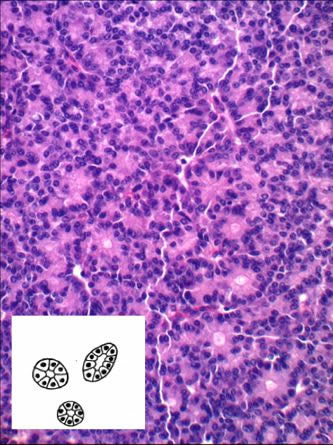

AI技術を基礎として、がんの成長過程をシミュレートします。がんは2人に1人が罹患する病気ですが、現在の医療技術をもってしても明らかになっていないことが多くあります。そこで,AI技術を活用し、がん細胞の成長過程を数理モデルにより近似させ、それらがどのように増殖していくかを解明します。図は膵臓がんを染色した標本画像ですが、その連なりを左下の模式図のようにモデル化し、その成長過程をシミュレートします。将来的にはコンピュータ上で、薬品の効能を確認するためのシミュレーションとして活用できます。